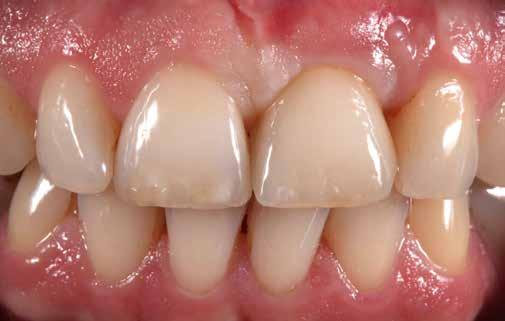

keltett. Az egyébként ideális tipikus formájú koronák esztétikailag optimális gingivakialakítást hoznak létre, a VMK korona kicserélése egyenletes fénytovábbítást tett lehetővé a papilláktól a korona felé és fordítva is. Míg a próba során még minimális sötét approximális háromszögek láthatók voltak, a végleges beragasztásra (Variolink Esthetic, Ivoclar Vivadent) már eltűntek (9. kép). A gingiva tökéletesen hozzásimult az IPS e.max ZirCAD Prime restaurációhoz.

Összefoglalás

Anyagválasztásunk újra tökéletesnek bizonyult. Kiemelkedő természetes hatása folytán akár leplezetlen IPS e.max ZirCAD Prime anyaggal is nagyon jó esztétikai hatású monolit restaurációk készíthetők. Itt az optimális alapot képezte, hogy leplező- és festékanyagainkkal elérhessük a kívánt hatást: hibátlan mosolyt és természetes szépséget. A páciens nagyon elégedett a kezelés eredményével – akárcsak mi magunk (10. kép).